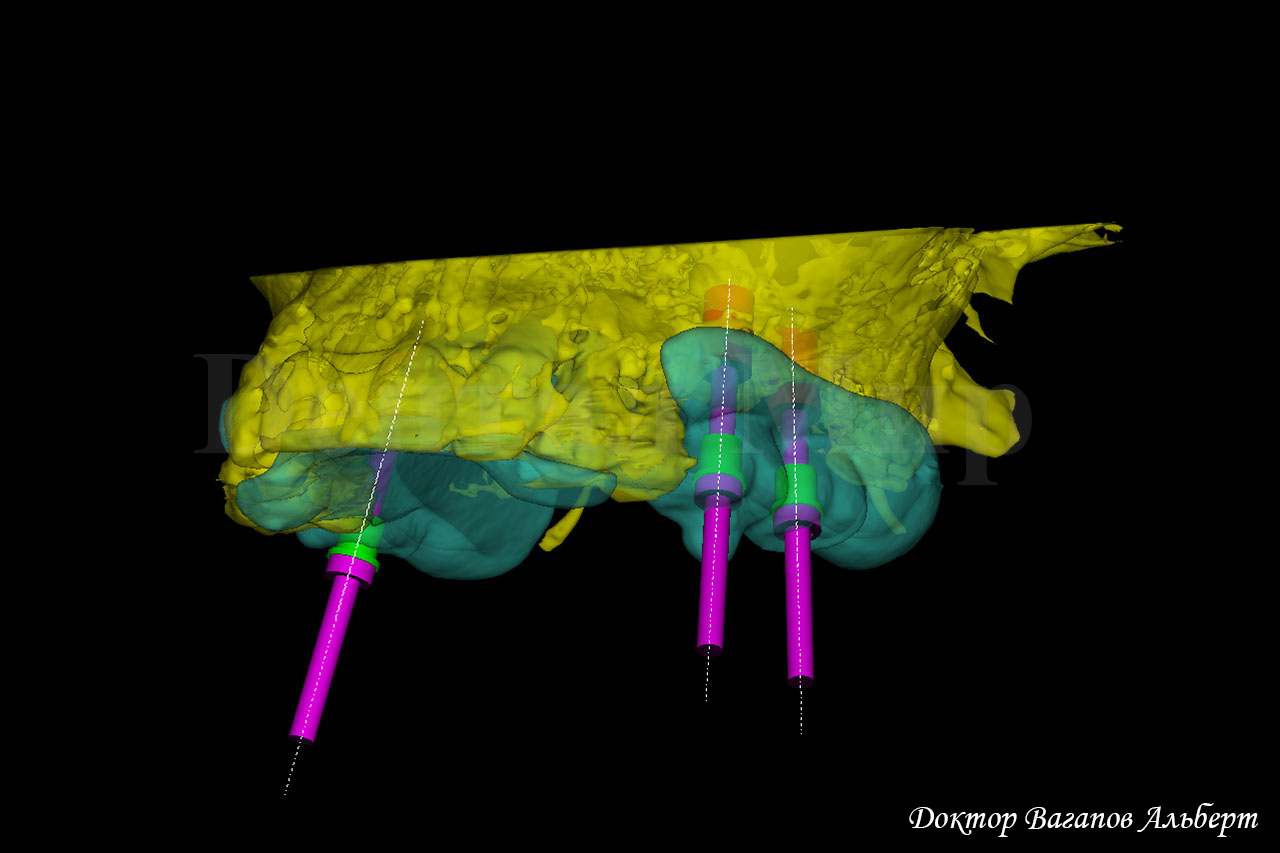

Когда устанавливается большое количество имплантатов, очень важно заранее все запланировать. Для этого были изготовлены рентгено-контрастные шаблоны и проведено 3D моделирование имплантации, определены имплантаты и места их установки.

На фото показаны изготовленные имплантационные шаблоны.